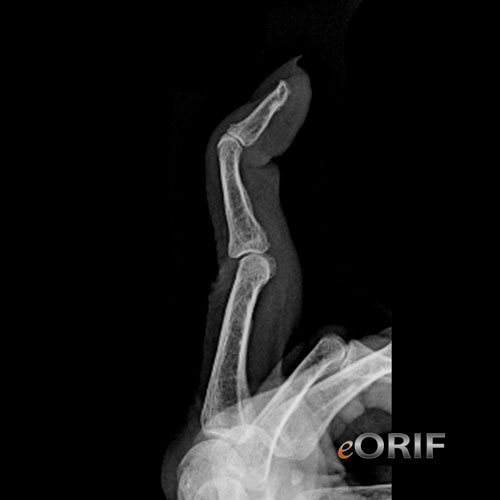

Mallet Finger Xray - Mallet finger : No visible changes on xray, changes seen on mri.

Mallet injury forced flexion of extended finger, with extensor tendon avulsion fracture at insertion site on examination distal phalanx is in flexed position with no active extension of dip joint ("extensor lag"). Management involves splinting the joint in neutral/ slight hyperextension (see at right); 17 / 8 / 21 patients from lgas of concern must have covid tests done prior to coming to prince of wales private hospial for admission or an appointment. An arthritic joint will show decreased space between the bones as the cartilage thins, bone spurs or calcium deposits on the edges of … 20.05.2021 · mallet finger sagittal band rupture carpal trauma radiocarpal fracture dislocation scaphoid fracture.

Joint leveling procedure (ulnar negative patients) radial wedge osteotomy or stt fusion (ulnar neutral patients) distal radius core decompression revascularization procedures. 25.02.2012 · "my finger doesn't work""my finger is bent""my finger won't straighten""my finger is drooped" these are several of the most common things i hear when patients come in with a mallet finger. An arthritic joint will show decreased space between the bones as the cartilage thins, bone spurs or calcium deposits on the edges of … Mallet injury forced flexion of extended finger, with extensor tendon avulsion fracture at insertion site on examination distal phalanx is in flexed position with no active extension of dip joint ("extensor lag"). Strictly avoid any flexion during the first. Osteoarthritis (oa) is the most common form of arthritis. Hyperflexion of the dip joints may result in avulsion of the distal phalanx base on the dorsal side. Currently consultations in the rooms are continuing but mask wearing is mandatory at all times. 15.11.2010 · "my finger doesn't work""my finger is bent""my finger won't straighten""my finger is drooped" these are several of the most common things i hear when patients come in with a mallet finger. Management involves splinting the joint in neutral/ slight hyperextension (see at right); Tenderness over dorsal aspect of dip joint. If there is a clinically evident mallet deformity, but no bone injury, do not make the mistake of thinking there is no significant injury. No visible changes on xray, changes seen on mri.